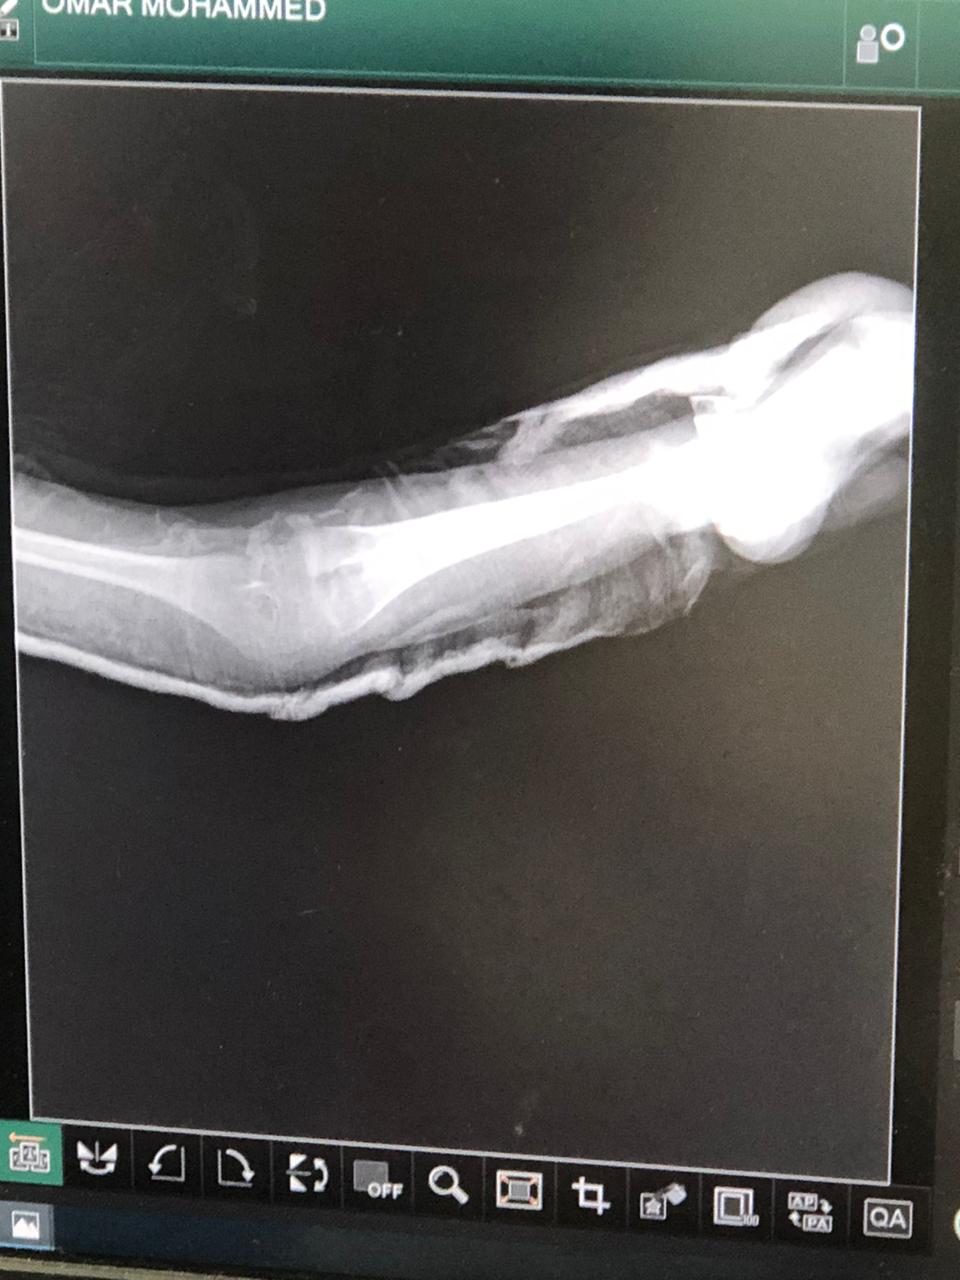

الم فى الذراع بعد الجبيره هل فيه مشكله فى الجبيره وقع على ذراعه وعملنا الاشعه ممكن توضيح للأشعة او تفسير للحاله